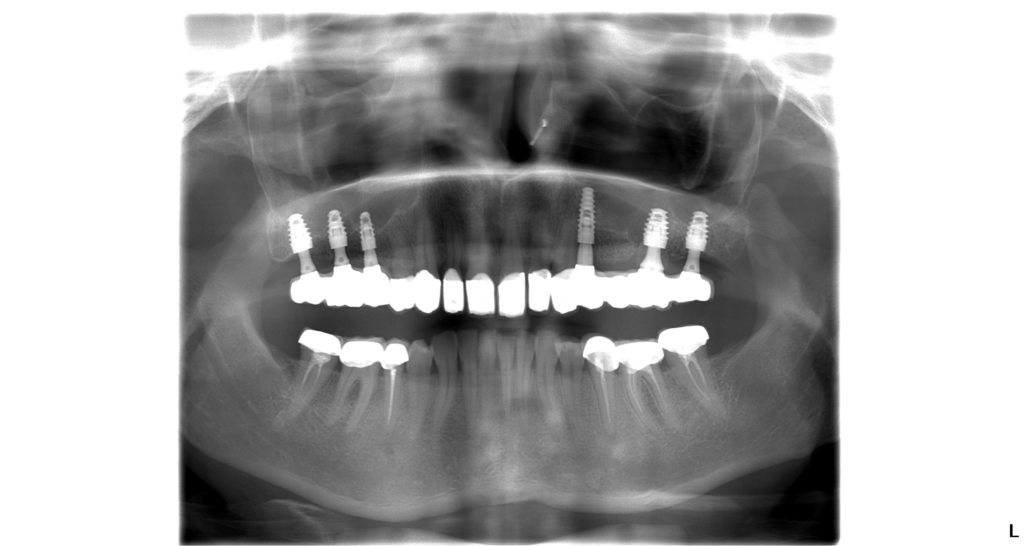

Mrs. Helen wanted to have a full set of teeth and a better-looking smile. She came to our dental clinic for the first time in April this year. Dr. Marek Salka made a treatment plan for her containing 7 E-max dental crowns for her upper front teeth, extraction of 2 of her teeth on her upper left hand side and altogether 6 dental implants for her upper jaw to replace missing teeth.

The doctor and the patient agreed to split the treatment into 3 visits. On the next day after the consultation she came to our dental clinic and Dr. Marek started with the treatment: he made a bone graft and sucessfully put all 6 dental implants into the patient’s jaw. Then he made a provisional bridge to protect those implants. Helen went home to give the implants some time to heal.

Three months later she came back to get her front teeth reshaped. Her final implant crowns and crowns for her front teeth were ready in 10 days.

When Helen came again the doctor took off the provisional bridge and fit all crowns in her mouth. After the final fitting she left us this lovely review: